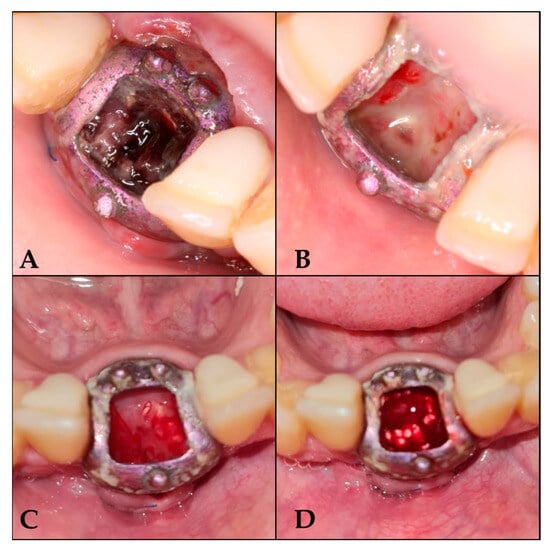

Closure was achieved through a combination of interrupted 3-0 non-absorbable sutures and approximation sutures at the crestal incision. The releasing incisions were subsequently sutured (Figure 2 and Figure 3A), completing the surgical procedure.

Figure 2. Preparation of the area for GBR with the barrier. (A) Area for barrier placement. (B) Full-thickness flap elevation. (C) Barrier fixation with screws. (D) Area for introducing the clot with tricalcium phosphate. (E) Suture of the releasing incision.

Figure 3. Follow-up sequence. (A) 7 days after surgery; (B) 16 days after surgery; (C) 25 days after surgery; (D) 42 days after surgery, once de-epithelialized and with tricalcium phosphate.

• Day 7: Irrigation with saline solution and removal of loose debris.

• Day 16: Loss of osteoid volume and necrotic blood was observed. De-epithelialization was performed without anesthesia to induce bleeding, and tricalcium phosphate was reapplied once the blood had coagulated.

• Days 25, 33, 42, 50, and 59: Repetition of the irrigation and de-epithelialization protocol.

• From the third month onwards: Follow-up visits every 21 days until 6 months, with irrigation protocol only (Figure 3).